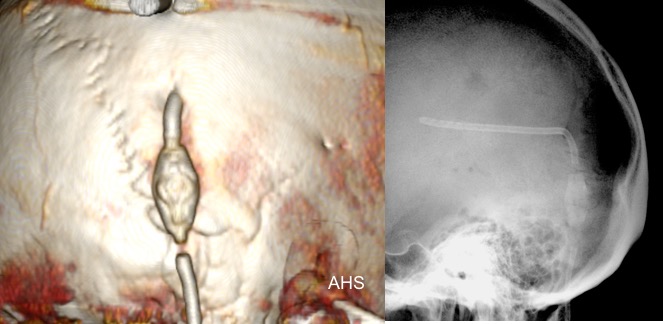

il existe un grand nombre de valves ; il n’est pas toujours aisé de les reconnaitre radiologiquement. voici la liste des plus courantes :

comment reconnaitre radiologiquement le type de valve ?